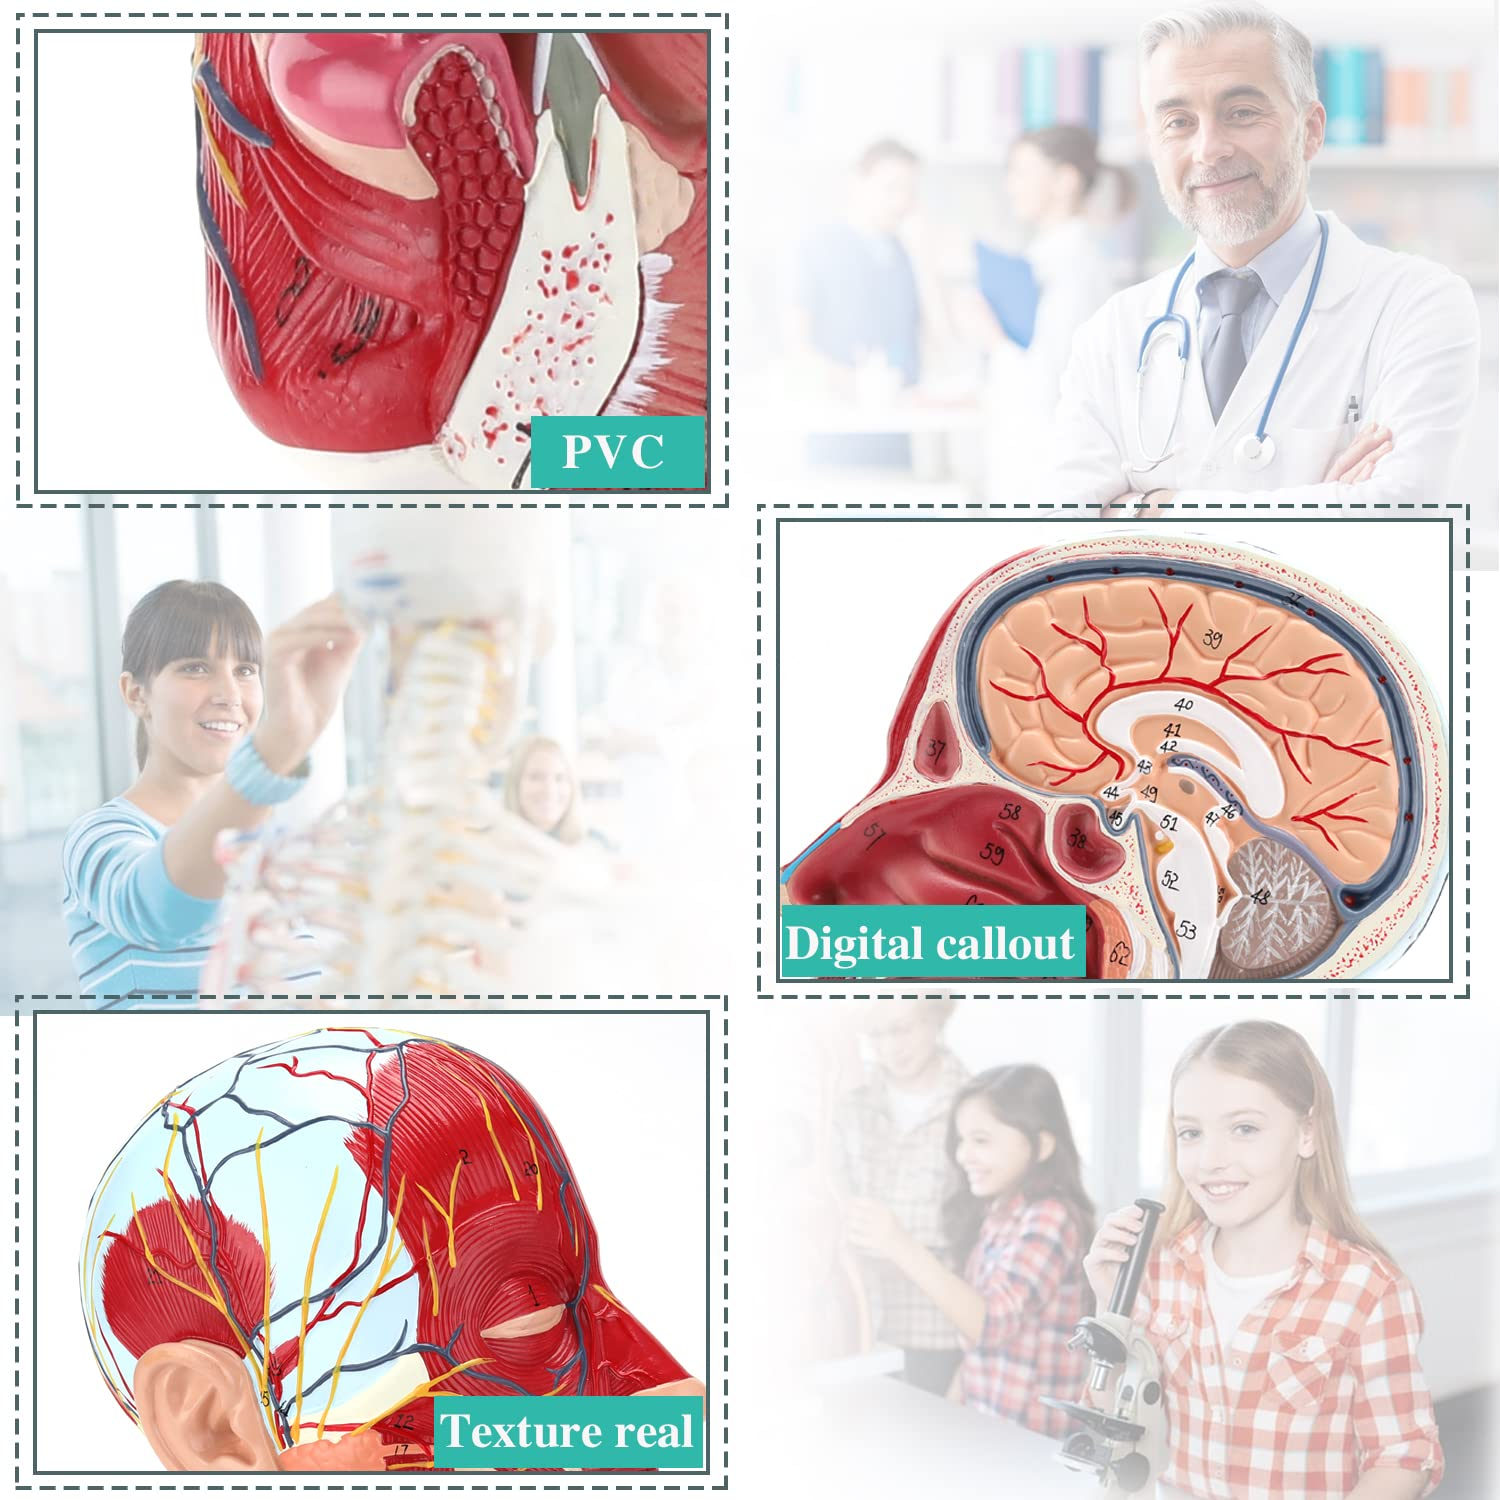

| Materjal | PVC |

【Mudell ta 'anatomija tal-moħħ ta' kwalità għolja, magħmul minn materjal tal-PVC mhux tossiku għall-ambjent, faċli biex jitnaddaf. Mudelli tal-anatomija huma miżbugħa bl-idejn u mmuntati bl-akbar attenzjoni għad-dettall.